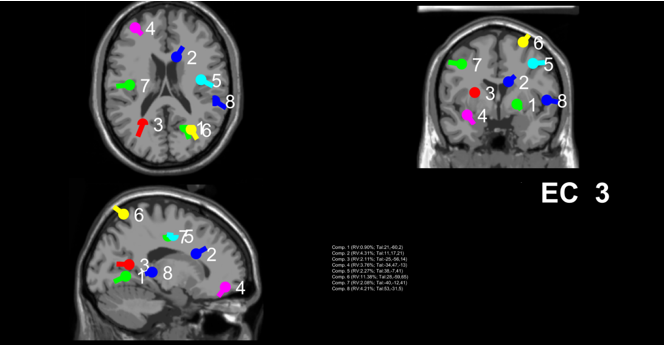

matrix is applied to the EEG, ICA generates the time-course of ICs, scalp topography maps and dipole locations for each IC. The time course indicates the strength of each component at any given time in microvolts, the scalp topography describes the strength of the IC at each electrode site, and the dipole shows the modeled location and positon of ICs in the brain. ICs will often display a dipolar distribution on scalp topography, which is indicative of a good component. This dipole is different from but consistent with the current dipole, which represents the activity of functional brain regions. These images in combination with other information allows us to distinguish IC components reflecting underlying true components of functional brain regions from artifacts. The corrected EEG is produced by multiplying the time-course of the ICs by the inverse of the weight matrix. The artifacts are removed by zeroing out their time-course in the multiplication process.